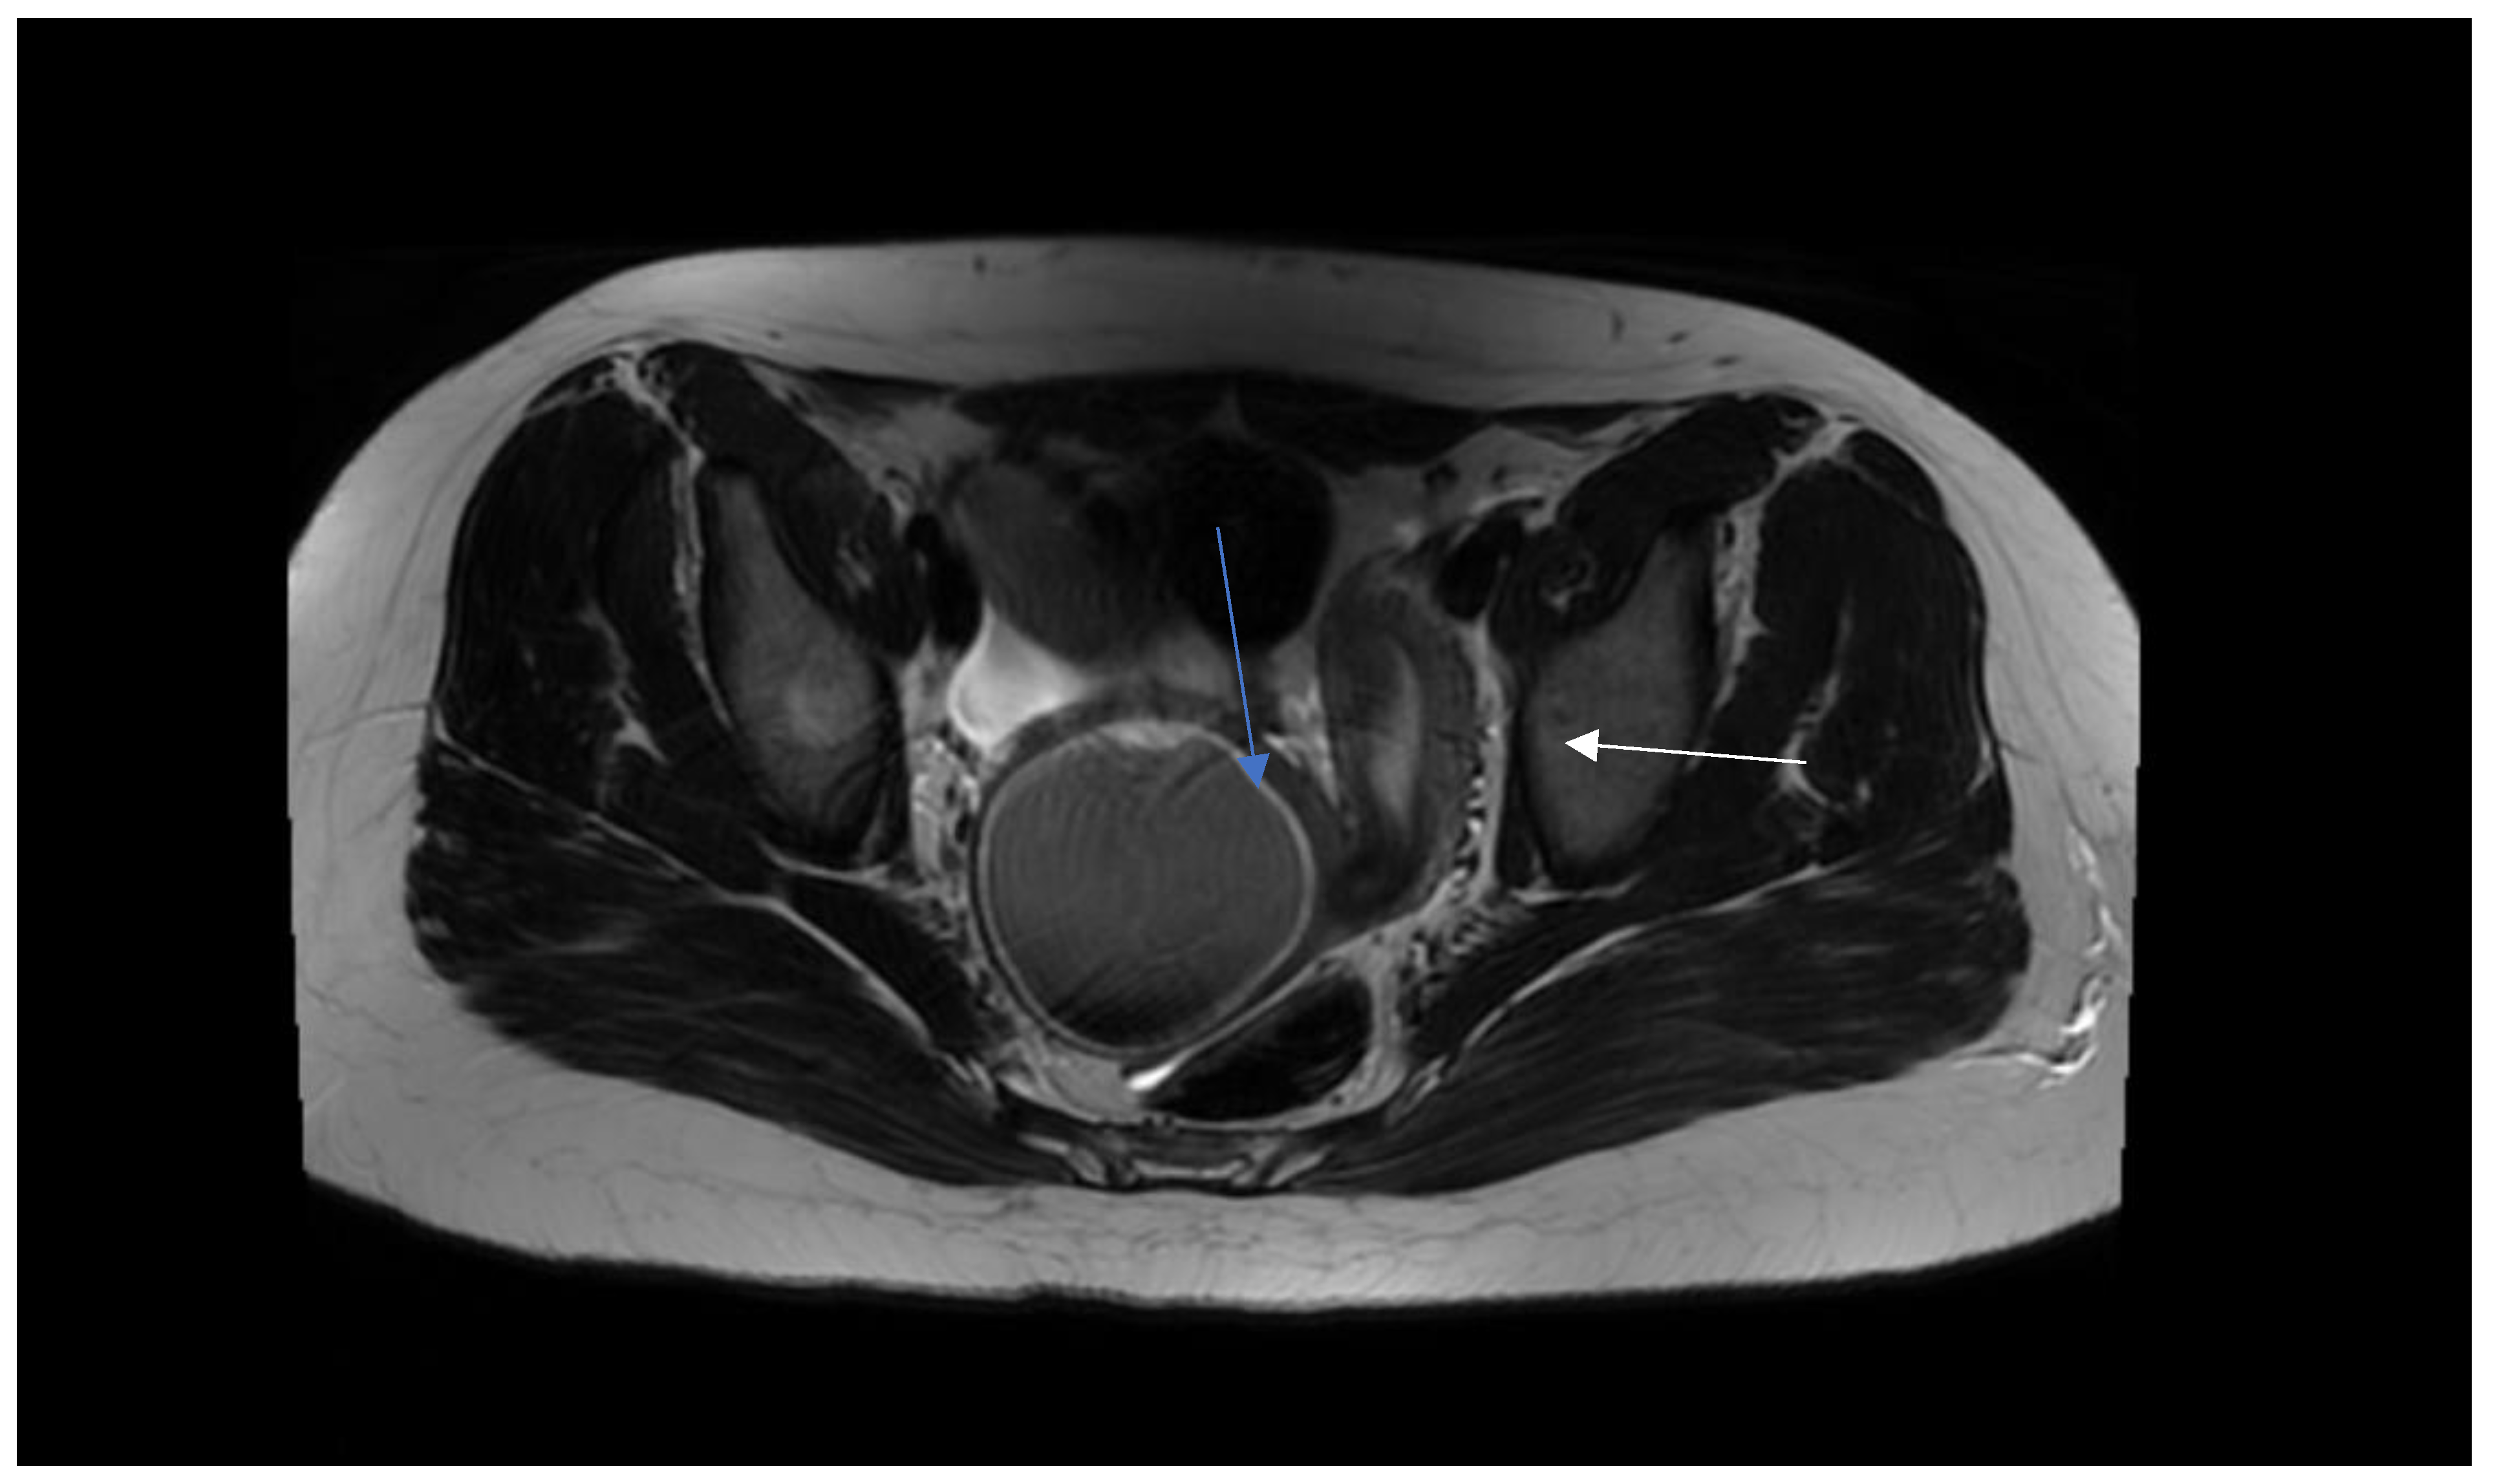

Step 1. Preoperative management Patients age (mostly occurs in young females), accurate history: time of first period, gradually increased symptoms, the appearance of symptoms during menarche, symptoms increase with each subsequent period, recurrent UTI, urinary disorders [8,9]. Perform physical examination. Next to the transabdominal US, transperineal and transrectal US can be useful in emergency situations to accurately access the place of abnormality [10]. MRI imaging should be considered as "gold standard in the diagnostic process [11]. Plan of the surgery and step by step proceeding is important while operating patients with urogenital abnormalities. As interdisciplinary collaboration of urologist and gynecologist is often necessary to treat correctly these patients. |